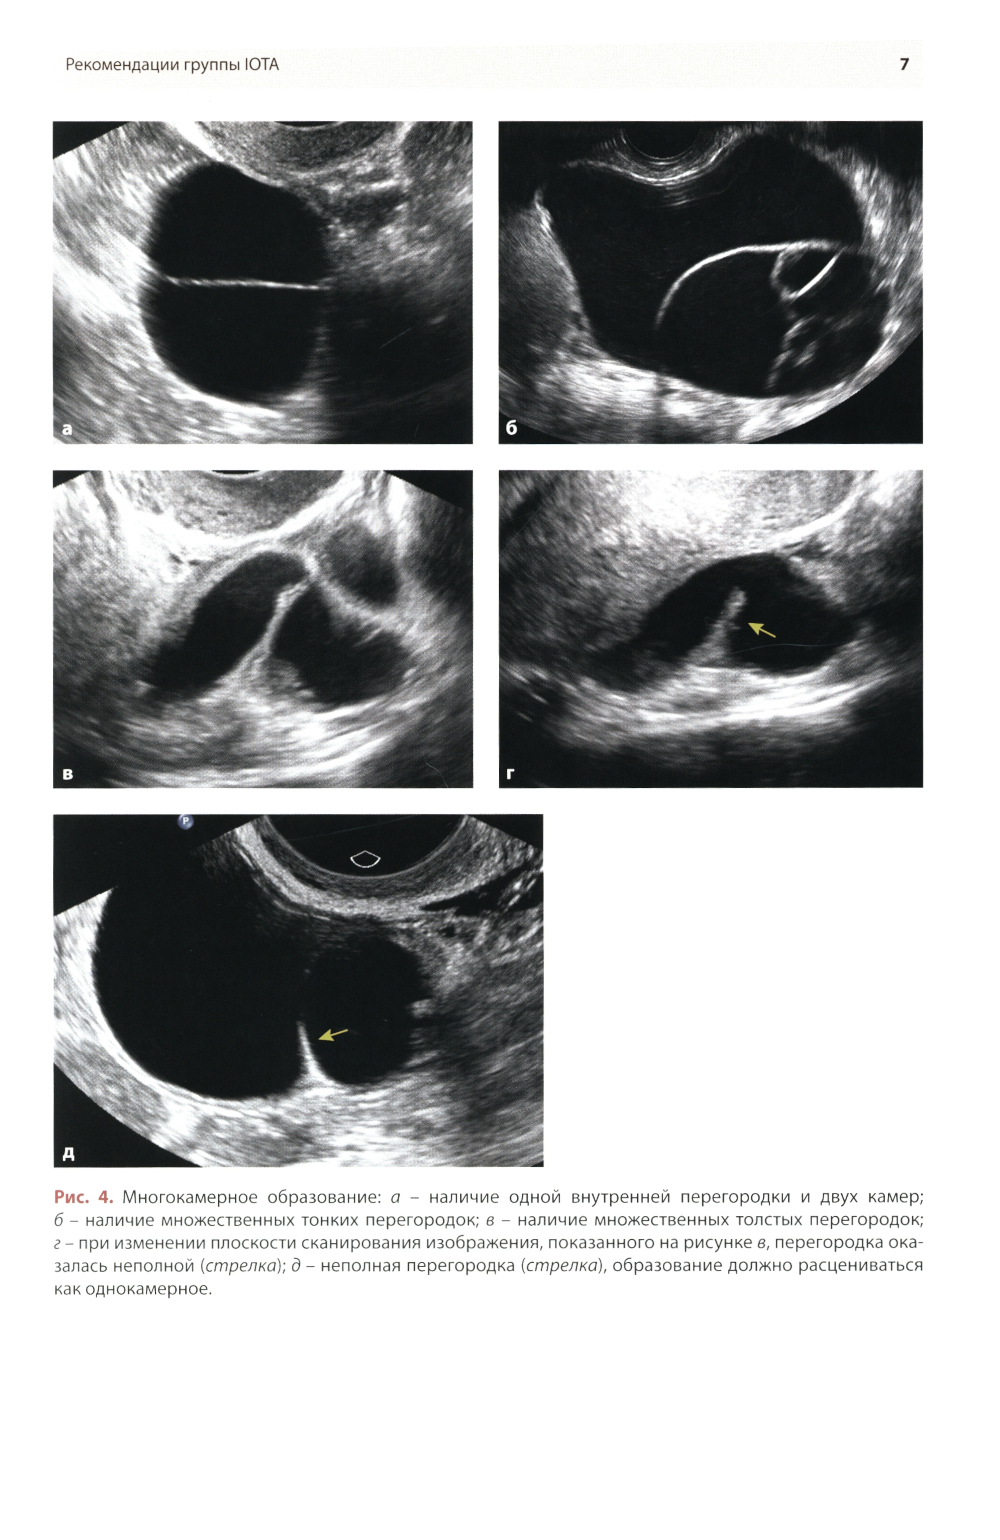

Методические рекомендации по стандартизации ультразвукового исследования с целью своевременной диагностики опухолевого процесса. Книга также включает вопросы дифференциальной диагностики физиологических изменений яичников, опухолевидных и опухолевых заболеваний и маршрутизации пациенток. Утверждено в качестве методических рекомендаций для проведения циклов первичной переподготовки врачей по ультразвуковой диагностике, тематического усовершенствования «Ультразвуковая диагностика в гинекологии», общего усовершенствования, ординаторов и аспирантов, проходящих обучение по направлению «Ультразвуковая диагностика, акушерство и гинекология».| Издательство | МЕДпресс-информ |